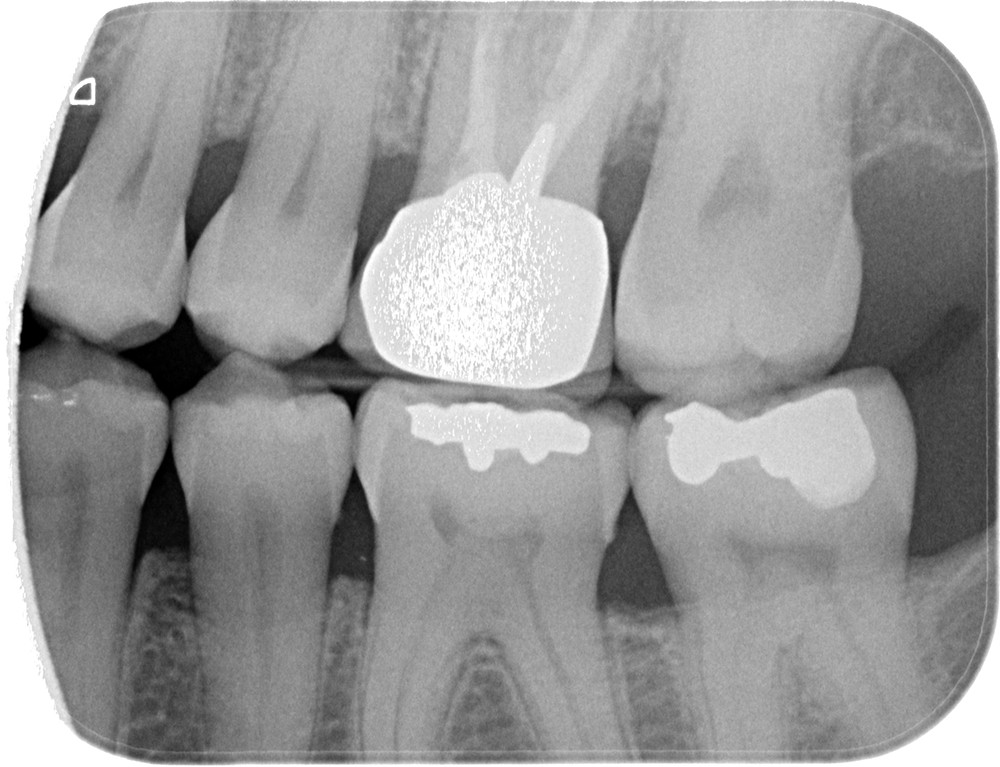

Radiographiquement, on observe une perte des cuspides et un aspect plan des faces occlusales (fig. 2a-b et 4a).

Cliniquement, les lésions d’abrasion sont caractérisées par des facettes lisses, une absence de convexité et des bords à angles vifs. La flexibilité du ligament alvéolo-dentaire va entrainer un frottement au niveau des points de contact, qui peuvent se transformer en surfaces de contact (fig. 2c-d, 3 et 4b-c).